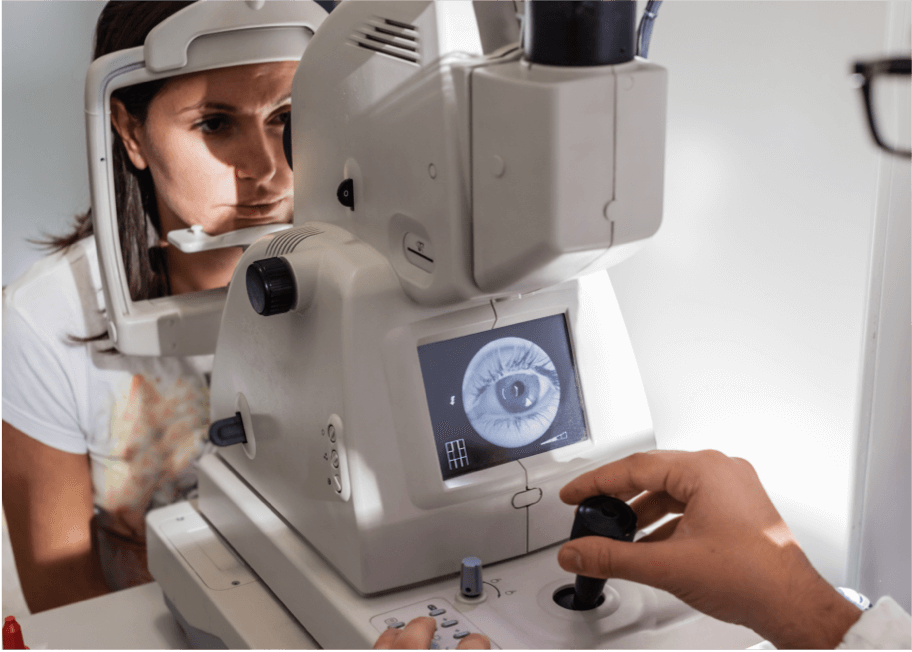

Oftalmoscopia con lámpara de hendidura

Este tipo de examen se utiliza habitualmente para diagnosticar la DMAE y se realiza con un microscopio oftálmico de lámpara de hendidura.5 La barbilla del paciente se apoya en un dispositivo de lámpara de hendidura, la luz se envía a través de una estrecha hendidura al ojo del paciente y el profesional examina el fondo de ojo a través de una lupa.5